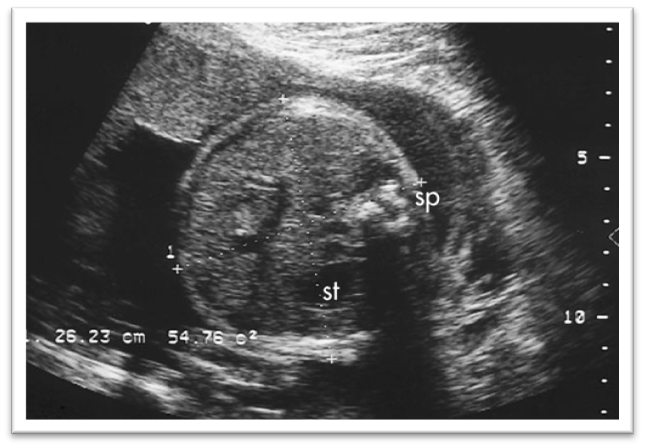

What is this image showing?

Pseudoascites